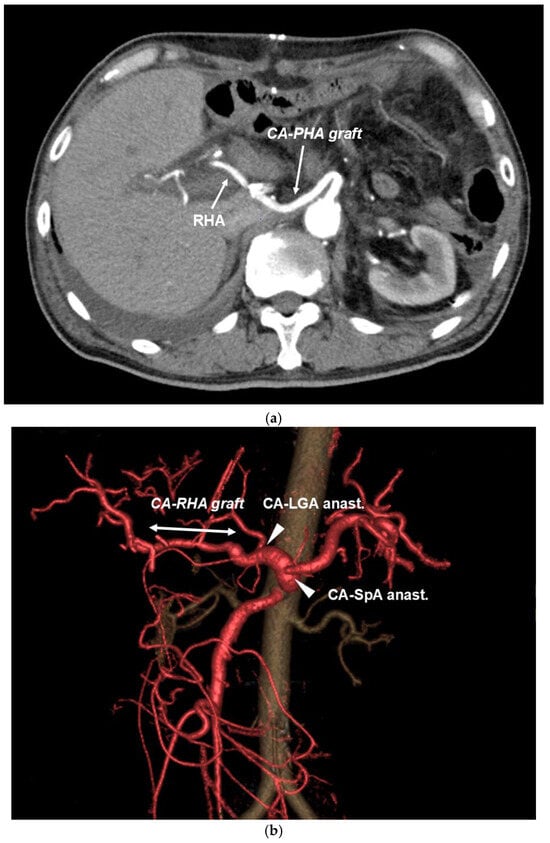

CA Reconstruction in TP-CAR+TG

| arterial reconstruction | CA-RHA | CA-PHA | CA-RHA | CA-PHAand SpA (Y-graft) | CA-RHA, CA-SpA, CA-LGA |

| invade artery | CHA, SpA | CA, CHA, SpA | CA, CHA, SpA | CA, CHA, SpA | CA, CHA, SpA |